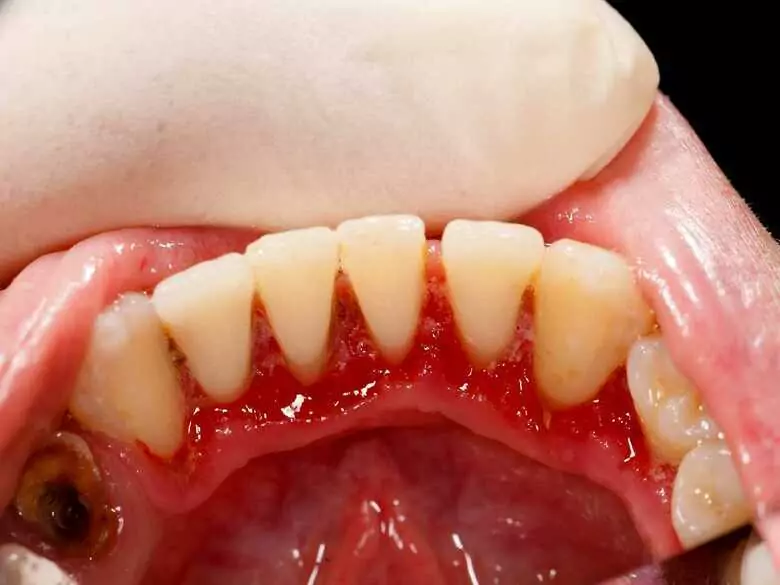

Die Symptome von Leukämie sind vielfältig und umfassen Appetitlosigkeit, Müdigkeit und geschwächte Immunität, aber auch Zahnfleischbluten. Letzteres gibt den Patienten in der Regel ein ziemliches Rätsel auf - warum haben Menschen mit Leukämie Zahnfleischbluten und welche anderen Veränderungen im Mund können im Verlauf dieser Krankheit auftreten?